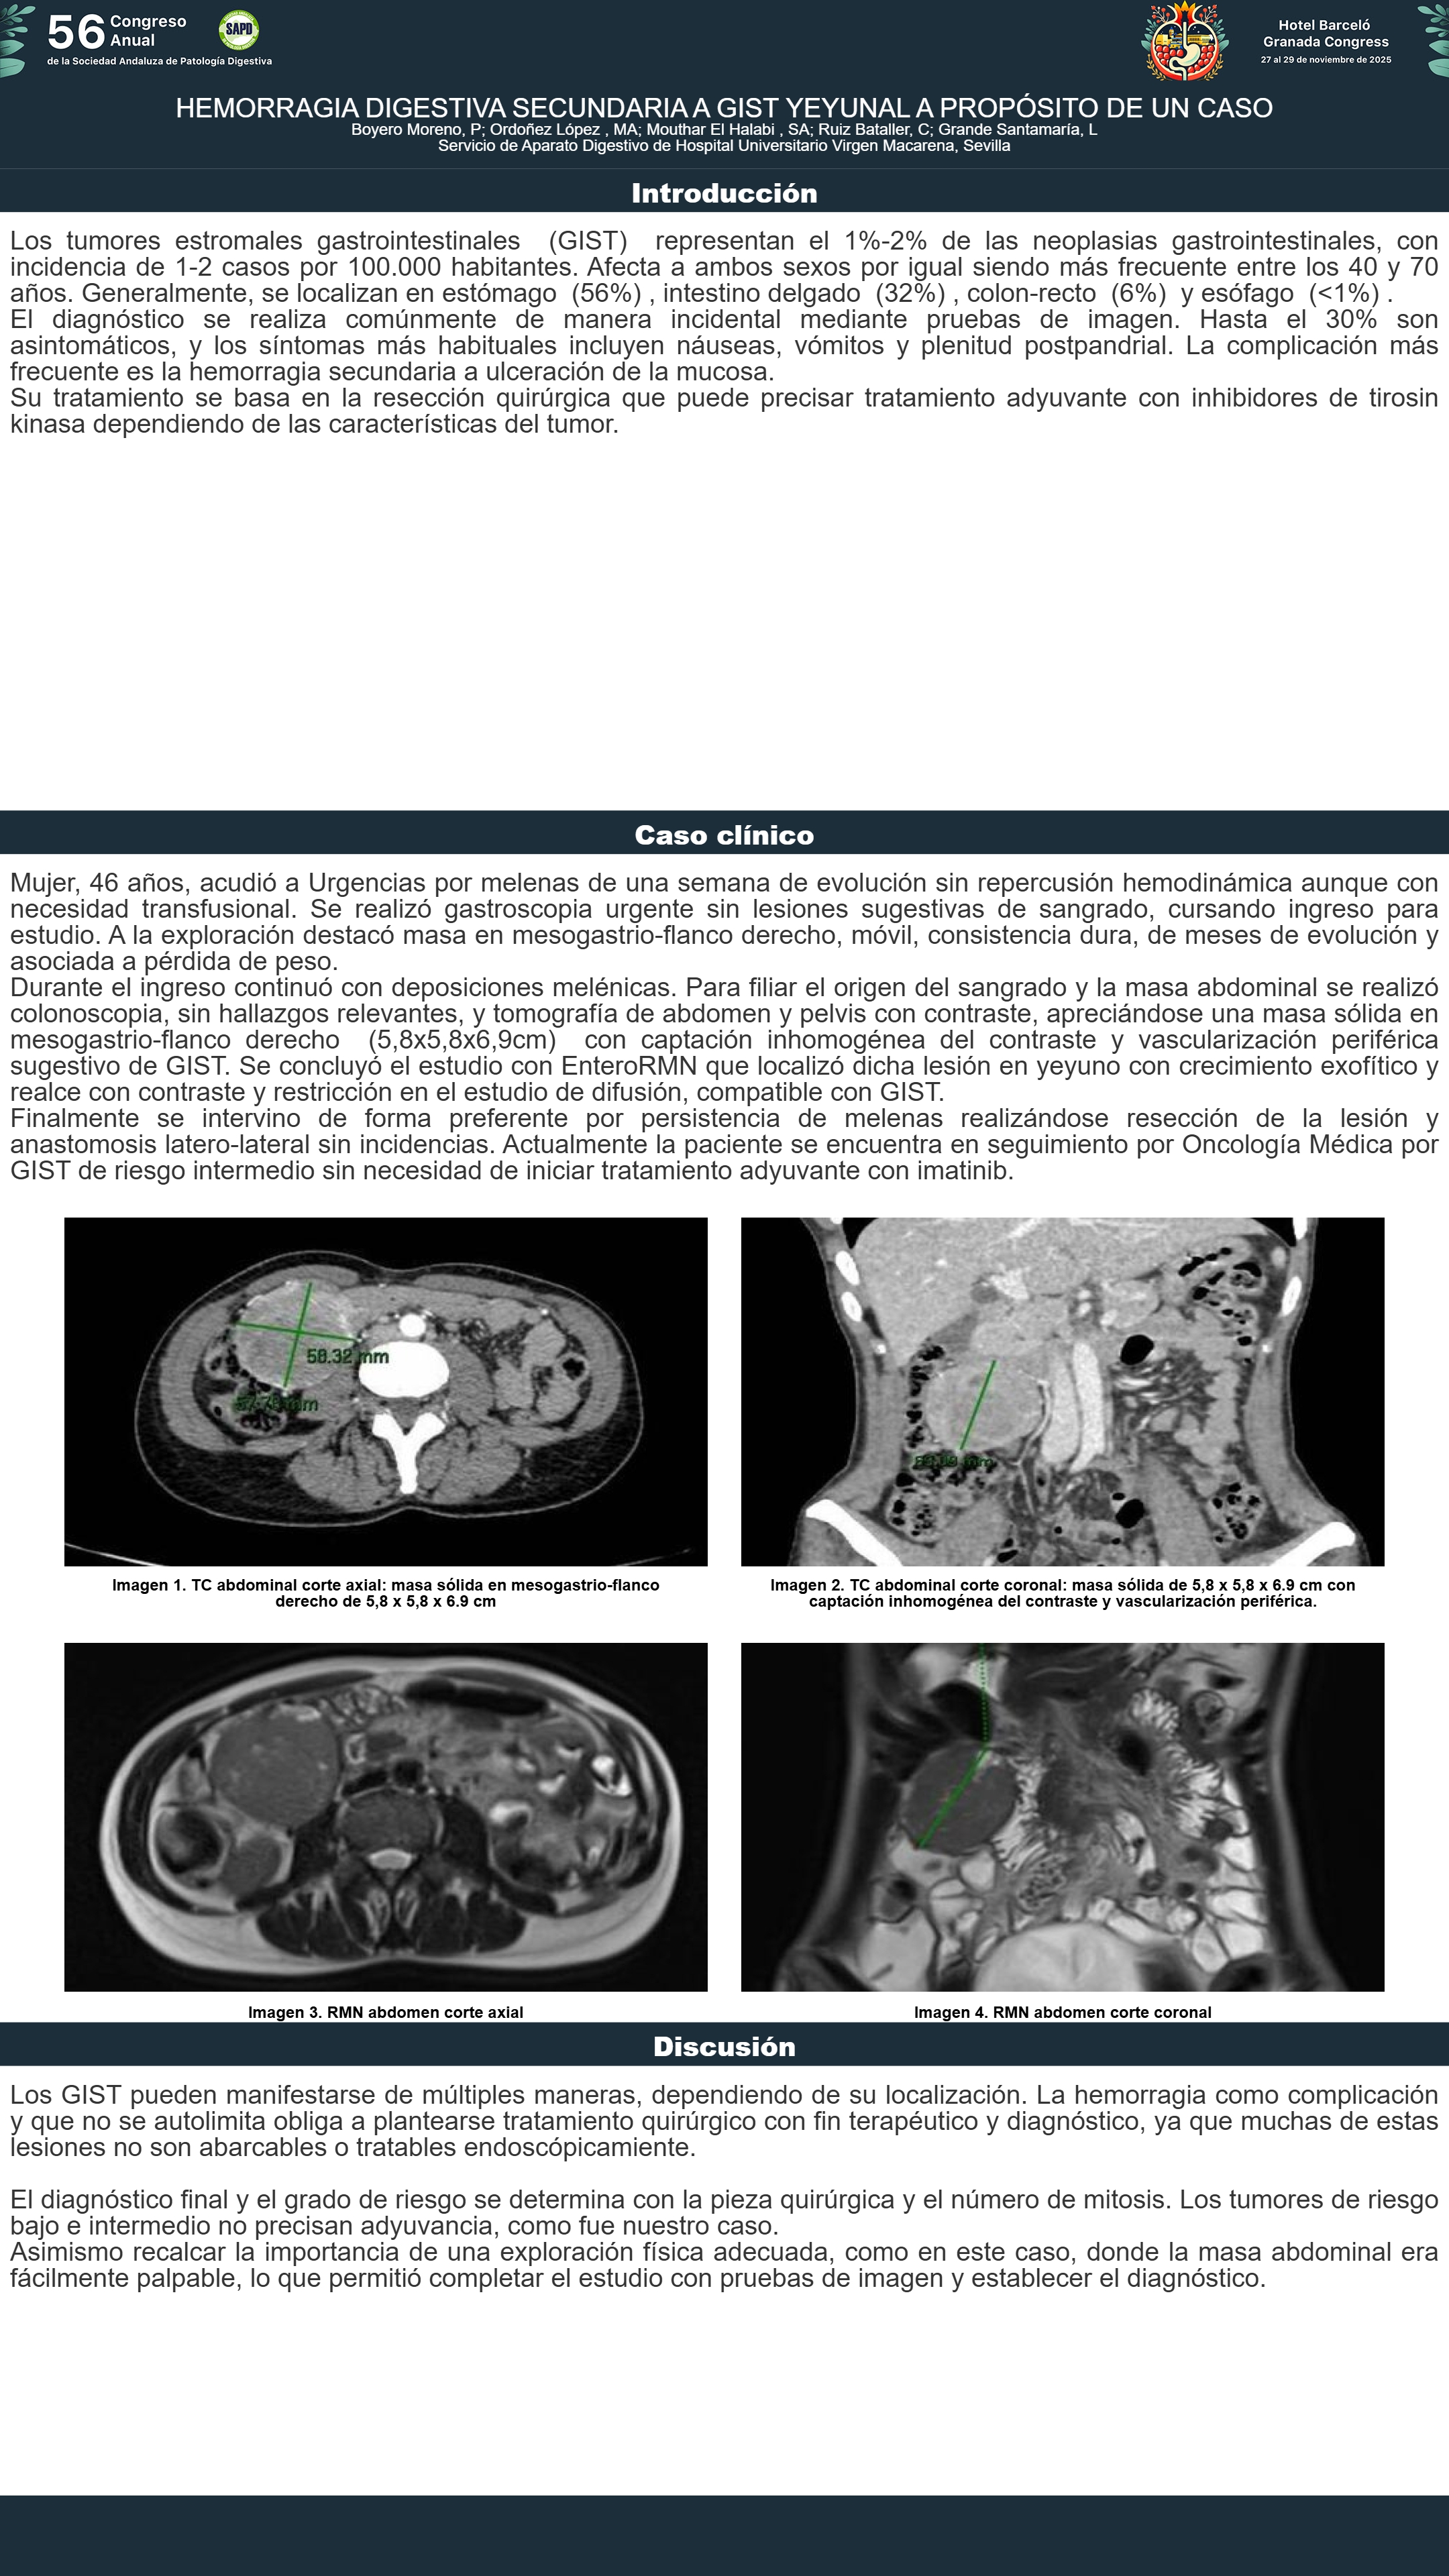

[CP-110] HEMORRAGIA DIGESTIVA SECUNDARIA A GIST YEYUNAL A PROPÓSITO DE UN CASO